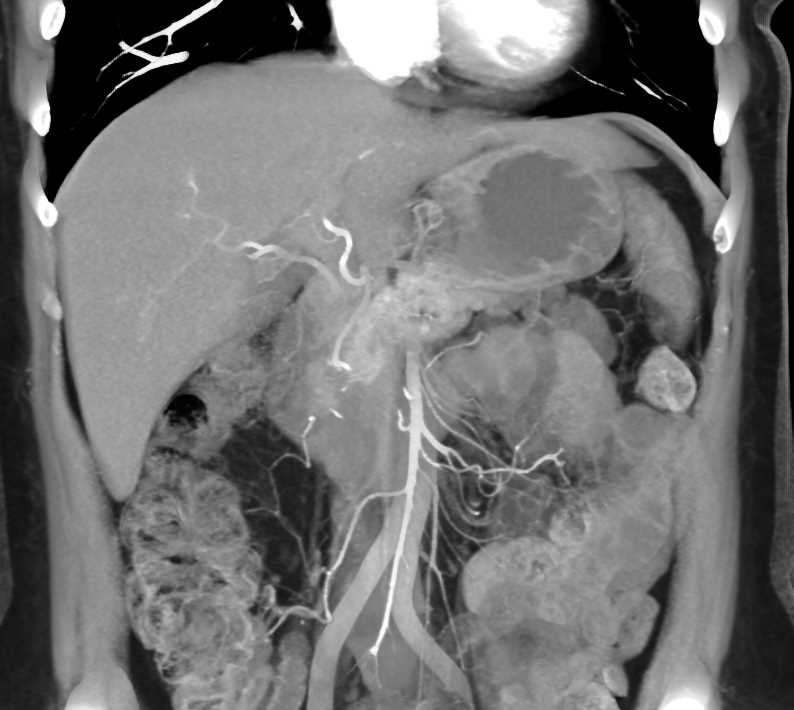

Adenocarcinoma of the Head of the Pancreas